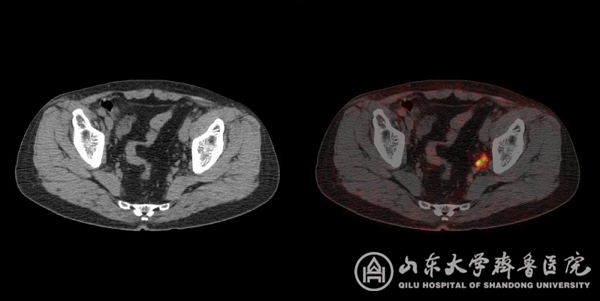

图2 直径只有4毫米的转移淋巴结

图3 CT未显示骨质破坏而PSMA PET/CT准确显示左侧髂骨骨转移,同时显示盆腔转移淋巴结。